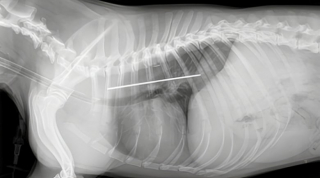

Plusieurs examens ont alors été réalisés, parmi lesquels des radiographies et une endoscopie. Le résultat avait de quoi surprendre. Lola avait dans son organisme un corps étranger long et fin. Ce dernier s’est avéré être un peigne de 20 cm, avec un manche pointu en acier. Par un incroyable miracle, aucun organe ne semblait touché. Il fallait néanmoins agir vite.

Le cas bien particulier du toutou a nécessité l’intervention de 2 grands spécialistes : les Dr Luca Motta et Harry Warwick. Leur expérience et leur expertise ont ainsi permis l’extraction du corps étranger en toute sécurité, le tout sans opération chirurgicale. Un véritable exploit ! Le soir même, la petite chienne mangeait normalement, et le lendemain, elle pouvait rentrer chez elle.